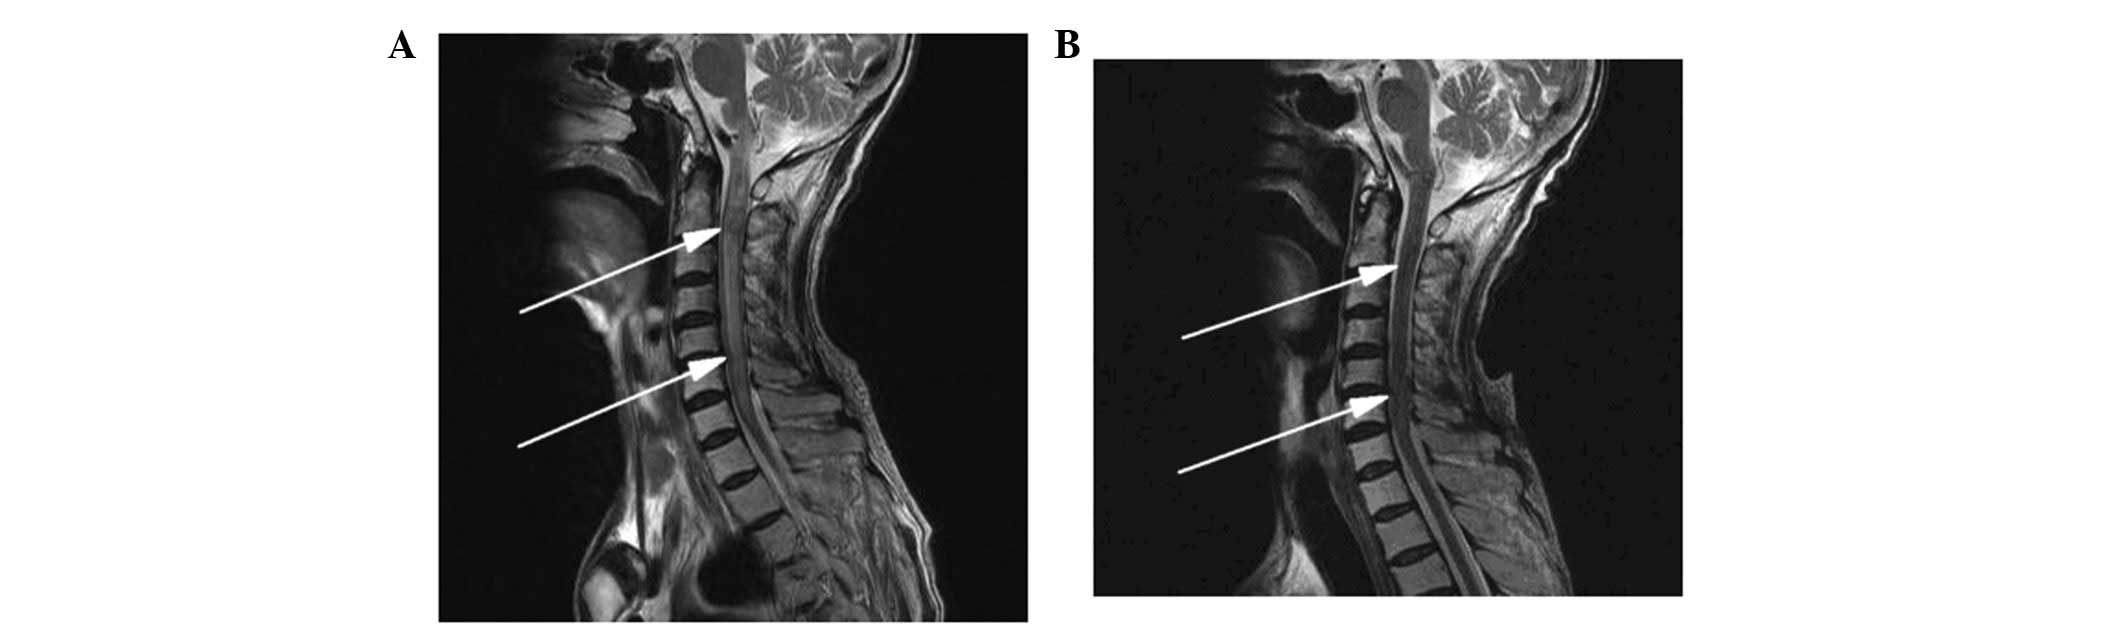

Comparison between the cerebral MR images of the esophageal cancer patient obtained prior to (MR 06-1-2009) and following (MR 10-15-2009) the metastasis. (A) Enhanced axial T1-weighted images and (B) axial T2-weighted images. Left (MR 06-1-2009), no abnormal signals were observed in the brain; and right (MR 10-15-2009), abnormal signals were observed in the right cerebellar hemisphere (indicated by the arrows). MR, magnetic resonance.

Diagnosis of central nervous system metastasis and treatment

The patient complained of constant occipital headache with slight pain in the bilateral upper arm and fatigue, but no nausea or vomiting, for 2.7 months after the treatment of the primary lesion. The Karnofsky performance status (KPS) score was 70 and no pathological reflexes were observed on physical examination. Brain MRI revealed two nodules (0.35 and 0.8 cm in diameter) in the right cerebellar hemisphere. The signal was slightly lower in the unenhanced T1-weighted images and slightly higher in the T2-weighted images. The lesions showed clear ring-like, uniform hardening on signal-enhanced scans, and mild edema was observed surrounding the larger lesion. The diagnosis was of a cerebellar metastasis from the esophageal cancer following treatment (Figs. 3–5). Following whole brain radiotherapy of a total dose of 30 Gy/20 fractions of 1.5 Gy per fraction by hyperfractionation (two fractions per day), the patient’s occipital headache was relieved, however, the neck numbness was aggravated. A cervical MRI examination revealed enlargement of the medulla oblongata and spinal cord, with slightly increased T1 and T2 signals. A signal-enhanced scan showed heterogeneous enhancement in a region considered to be the metastasis. The patient continued with the planned whole brain radiotherapy, together with nedaplatin chemotherapy (40 mg on days one to three of the radiotherapy period). At the end of the first period of chemotherapy, the patient’s occipital headaches were alleviated and the neck numbness was markedly improved. One month later, the patient’s head and neck symptoms had further improved and a neck MRI revealed that the abnormal signal foci in the medulla oblongata and cervical cord had also markedly improved (Figs. 6 and 7). To strengthen the effects of the treatment, the patient was treated with palliative radiotherapy (total dose of 26 Gy/13 fractions of 2 Gy per fraction) to the cervical spinal cord. Following treatment, the patient’s head and neck pain and numbness symptoms had almost disappeared. The patient was discharged with oral etoposide (VP-16) capsules (50 mg daily for 20 days).